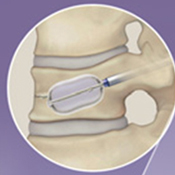

BKP

風船をしぼめた状態で設置して、

ゆっくり風船を膨らませます。

復元します。

スペースにセメントを注入します。

BKPと同様に細い筒から骨折したせぼねに風船をしぼめた状態で設置して、ゆっくり風船を膨らませます。風船でステントを広げてスペースを作り、風船を取り出してステントとともにセメントを注入します。